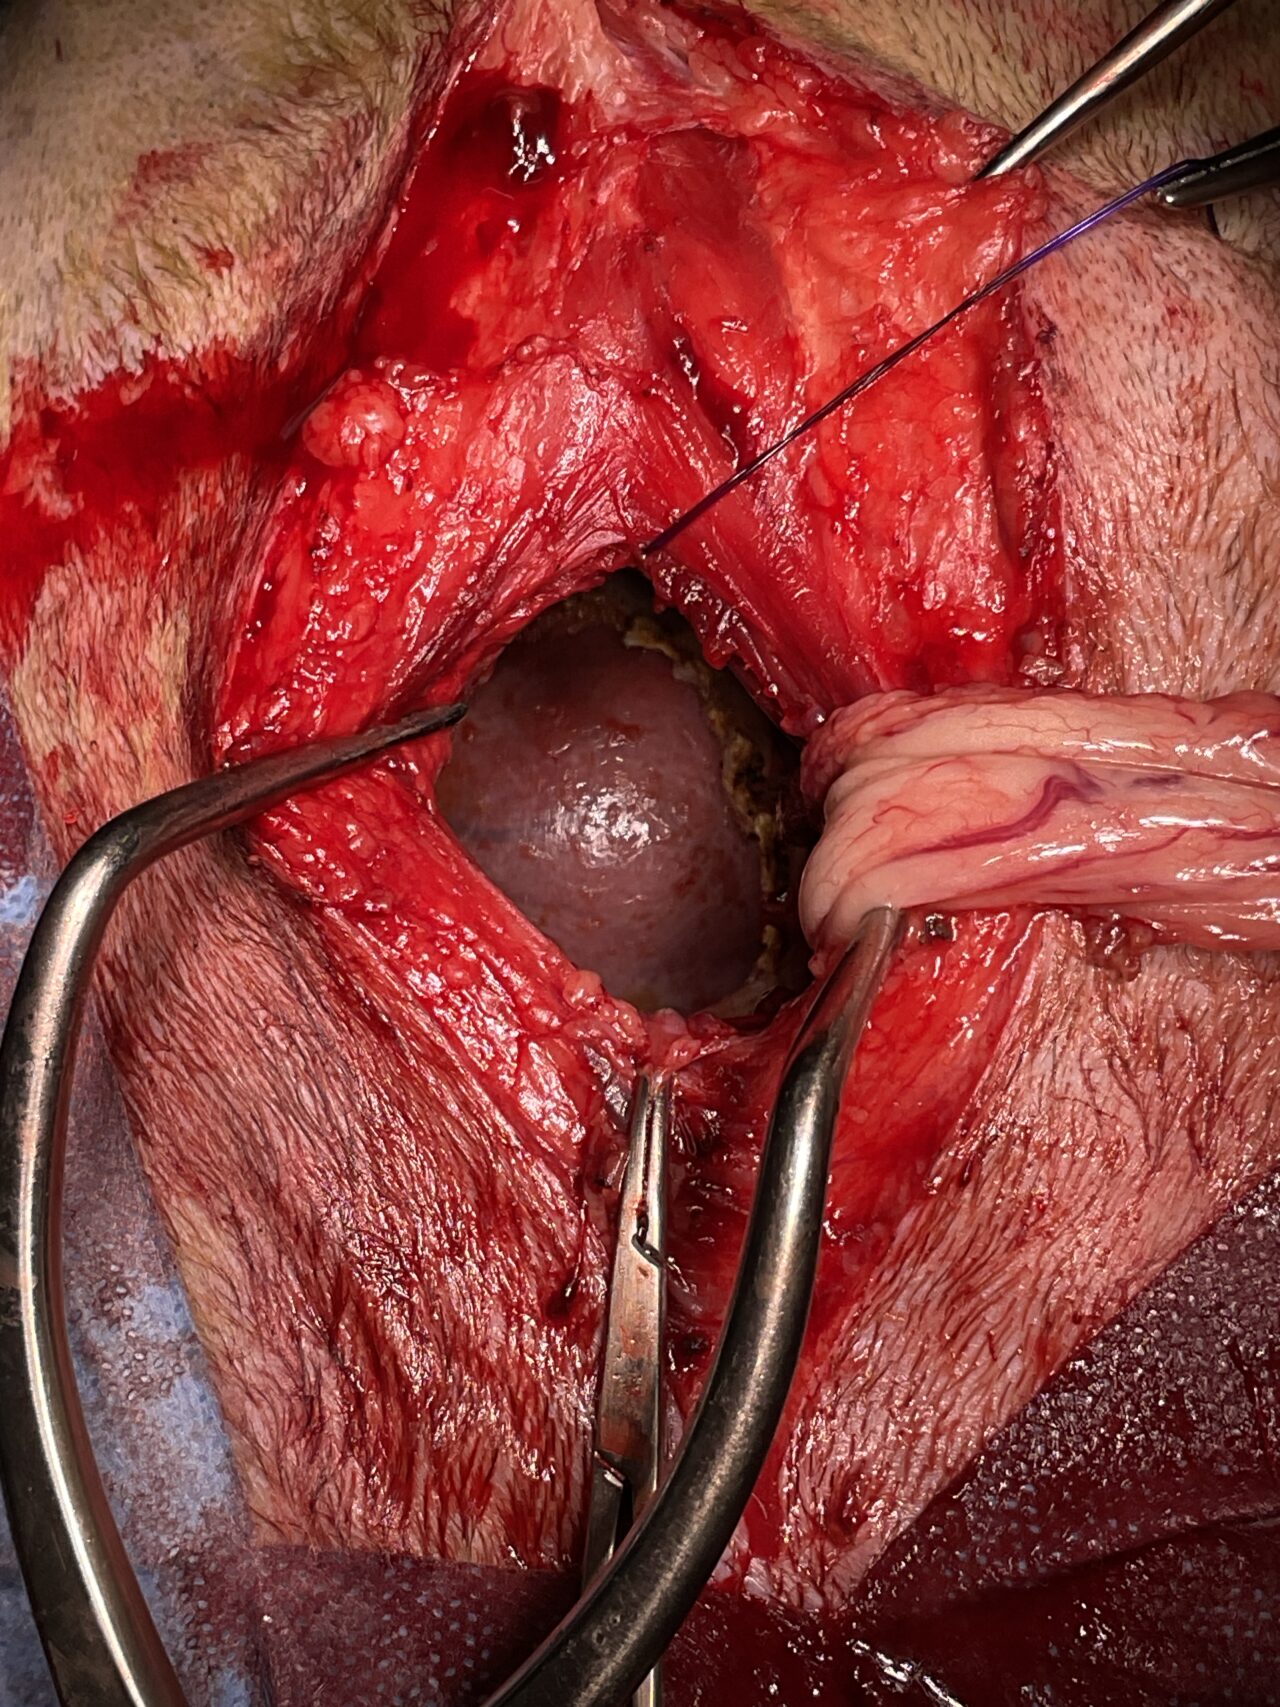

胃捻転整復+心膜切除術

高齢(12歳)のアフガンハウンドが吐きたそうだけど、何も出てこない。次第に起立出来なくなったとのことで夜間に救急で来院しました。症状とエックス線検査から胃捻転と診断しました。また聴診時に心音は遠く、聴取出来ませんでした。胸部エックス線検査においてムーンハートが確認されました。超音波ガイドで出血性心のう水を2リットル抜去しました。バイタルサインが落ち着いたところで胃捻転整復術を実施しました。その後も出血性心のう水は貯留傾向にありました。高齢であることから血管肉腫が疑われましたが、各種画像診断においても腫瘤の存在はなくまた細胞診においても血管肉腫の可能性は低いものと判断しました。胃捻転から2週間後、心膜の生検と再発性の心膜貯留を回避する目的で心膜切除術を実施しました。心膜は顕著に肥厚し、線維化を伴っていました。病理検査の結果をもとに内科療法を併用する予定です。高齢ながら頑張ってくれました。